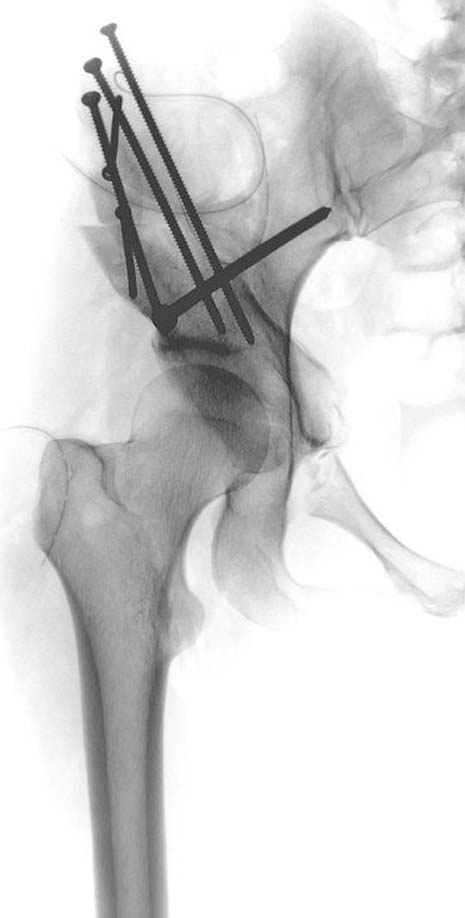

Рис.1 Трехмерная модель тазобедренного сустава с аналогом связки головки бедра. Заметно, что из торца головки выходит капроновый шнур, который с одной стороны прикрепляется к ножке бедренной части модели, а другой его конец, проходя через головку и прикрепляется к вертлужной части модели. Динамометр оказывается не нагруженным, так как аналог связки головки бедра замыкает подвижный узел модели во фронтальной плоскости.